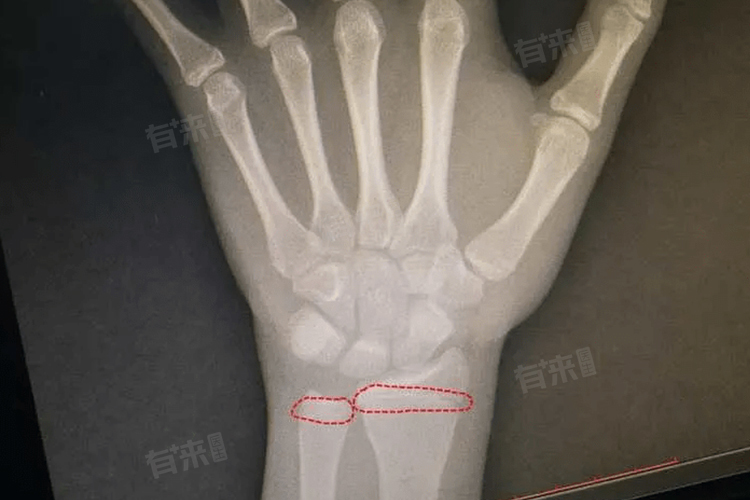

1、手腕部:手腕部集中众多小骨骼,是判断骨龄闭合的常用部位。通过拍摄左手手腕X光片,可清晰观察到桡骨、尺骨远端骨骺以及各掌骨、指骨骨骺的发育情况。骨骺与骨干之间的软骨缝隙逐渐变窄直至消失,表明手腕部骨龄趋于闭合,反映整体骨骼生长进入后期阶段。